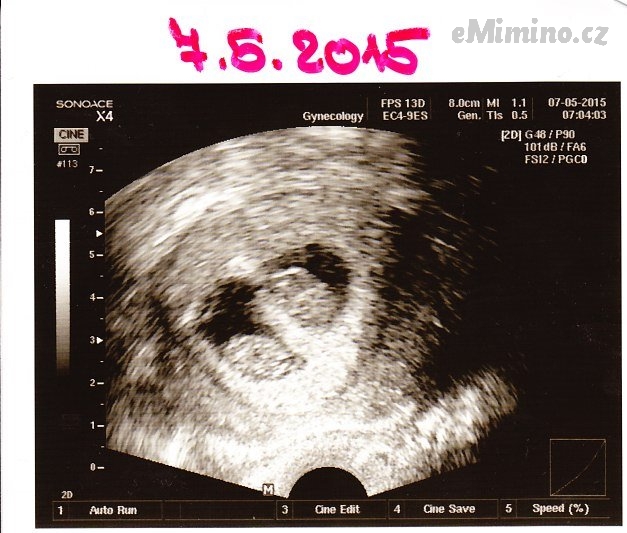

7. května 2015 (8+4)

– první miminko 8+1, 1.95cm

– druhé miminko 8+1, 1,73cm